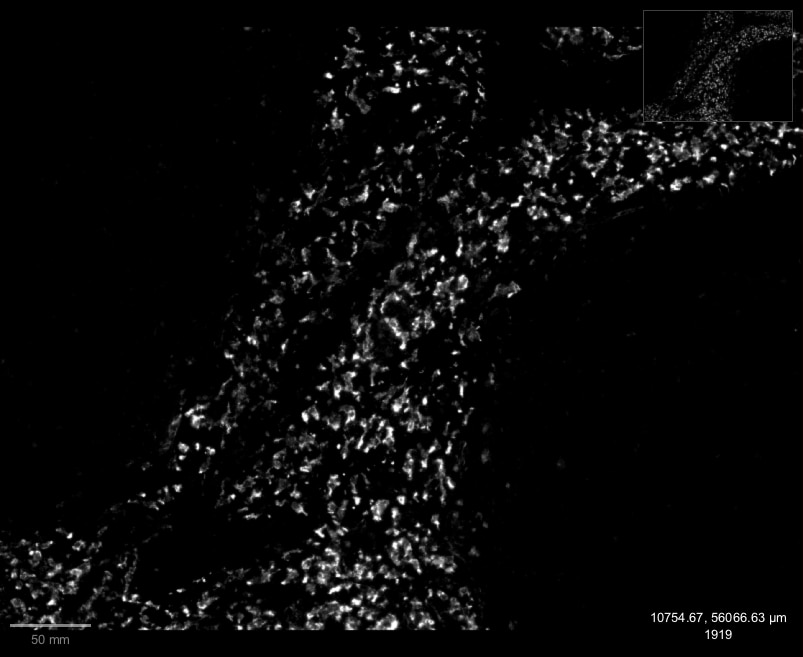

Enlarge |

IHC-Fr | Mouse | 01/18/2023 |

Enlarge |

IHC-P | Mouse and Rat | 03/16/2018 |

|

IHC-Fr | Mouse | 01/07/2015 |

| Verified Customer 01/18/2023 |

| Application: | IHC-Fr | |

| Species: | Mouse |

| Application: | IHC-P | |

| Species: | Mouse and Rat |

| Application: | IHC-Fr | |

| Species: | Mouse |